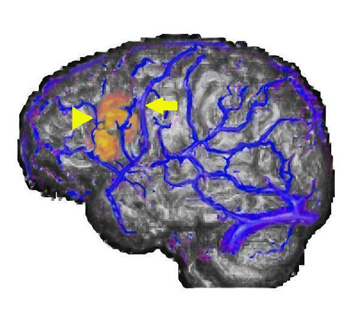

Caso 1

Niño diestro de 11 años de edad con epilepsia intratable y hemiparesia izquierda. Al paciente se le realizó un mapeo del lenguaje como parte de su preparación para la cirugía de epilepsia con una "tarea de fluidez semántica".

Representación tridimensional de superficie y vistas ortogonales. Las imágenes muestran la activación del área de Broca a lo largo de las pars orbitalis, triangularis y opercularis del hemisferio izquierdo. También se observa la activación en las áreas visuales, posiblemente relacionada con estrategias visuales. En algunas ocasiones, como en este caso, se observa la activación de los ganglios basales. La activación puede estar localizada en una imagen que incluye la corteza, la fisura silviana, la fisura calcarina, los ventrículos laterales y a lo largo de la línea media.

Caso 2

Niña diestra de 11 años de edad con epilepsia persistente intratable sometida a resección frontal izquierda parcial. La paciente fue sometida a un mapeo del lenguaje mediante RMf.

| Vista lateral izquierda |

Vista rostral superior izquierda

Estas imágenes complementan el caso 2 presentado en "Representación de superficie". La activación se obtiene con una tarea de "generación de verbos" en el área de Wernicke, no solo a lo largo de la superficie cortical sino de forma profunda a lo largo de las circunvoluciones.